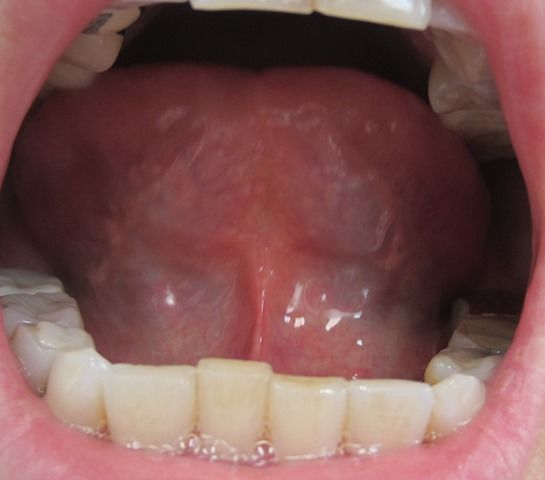

【2013年8月30日 漢方薬服用22日後の舌の裏】

筋が潤い柔らかくなりますと舌も柔軟になり上にしっかりあげられるようになります

静脈血管に黒い部分は於血毒素 炎症 火です

黒い色は於血 毒素 火 炎症 です。

※追記※関西相談会で撮影

【2013年9月21日・漢方薬服用44日後の舌の裏】